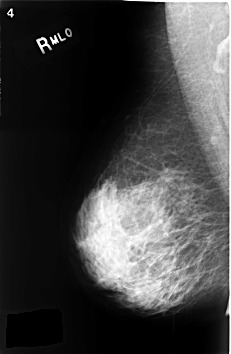

C_0343_1.RIGHT_MLO

RIGHT_MLO LINES 4600 PIXELS_PER_LINE 2992 BITS_PER_PIXEL 12 RESOLUTION 50 NON_OVERLAY